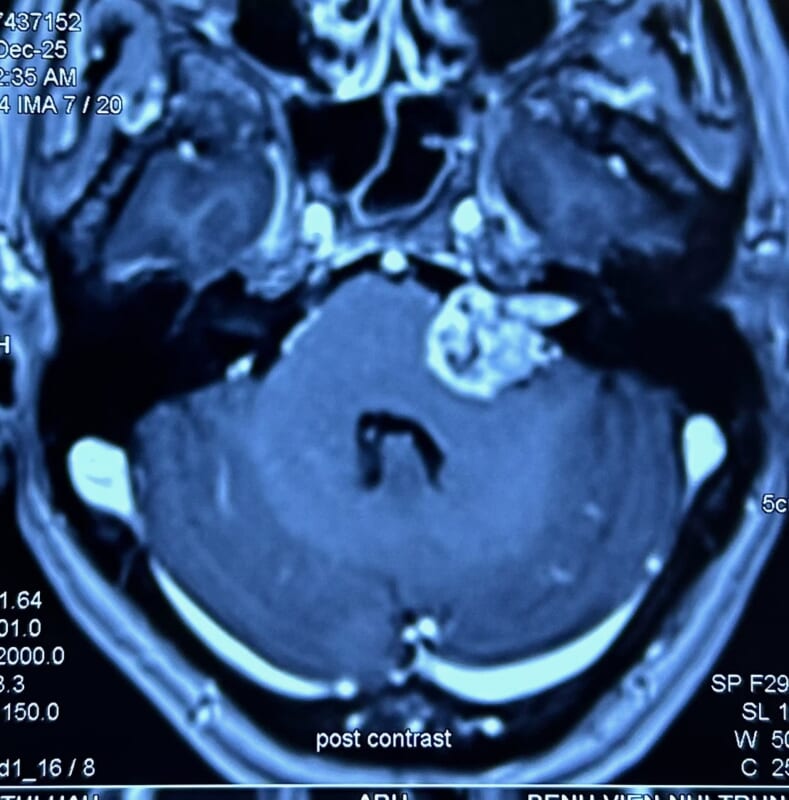

ハノイでの症例です。聴力低下にて発見された左聴神経腫瘍。サイズはそれほど大きくありませんでしたが、血流が豊富、かつ脳幹との癒着も強く、摘出は容易ではありませんでした。なんとか顔面神経機能を温存し、全摘出できました。